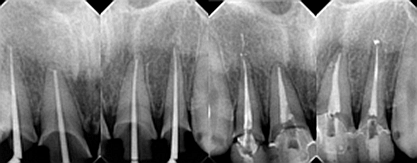

治療是從5月份開始的,醫(yī)生給我的主人驗了血,做手術前的準備,還給我們都用超聲波好好的都洗了個澡,把之前依附在我們身上的牙結石都沖了個干凈(齦上潔治術)。治療先從我和其他3個兄弟開始。在麻藥的作用下,我們兄弟4個都被打開了身體,去除了已經被蛀牙破壞的牙體,做了根管治療。

第二次治療是半個月后,這次做了根管充填后將覆蓋在我們身體上的一部分牙齦切除,讓我們埋于牙齦下的身體暴露了一部分,也就是醫(yī)生說的冠延長術。這是為了讓我們變得美觀一些。

根管治療

冠延長術

兩周后,主人帶我們往醫(yī)院拆線,取模,比色,為我們重新量身定制了一套堅固的“外套”。

第5次復診的時候,終于讓我們4個兄弟恢復了正常的容顏。